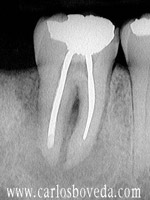

Video de un Retratamiento de Conductos en Una Sesión - (formato Quicktime)